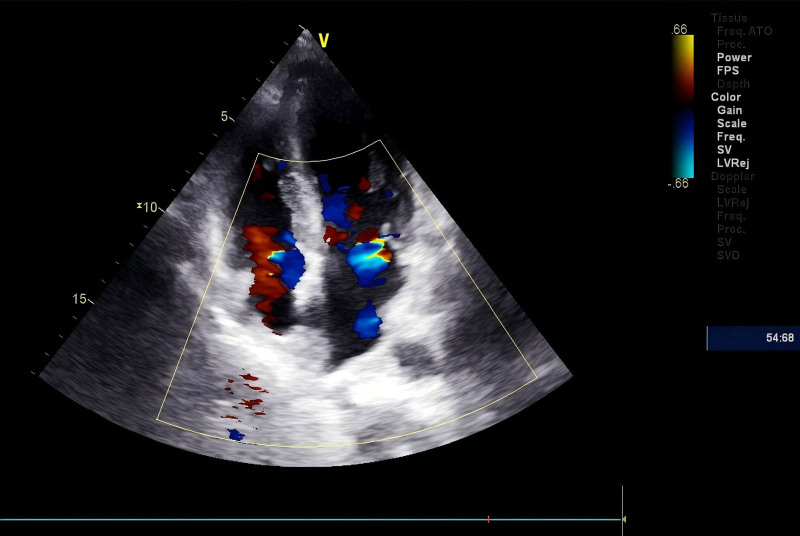

Diagnoses: Cardiac magnetic resonance imaging revealed findings indicative of AC, including left ventricular hypertrophy, diffuse delayed enhancement, and atrial enlargement. The diagnosis of immunoglobulin light chain amyloidosis was confirmed by endomyocardial biopsy, which was positive for κ light chains.